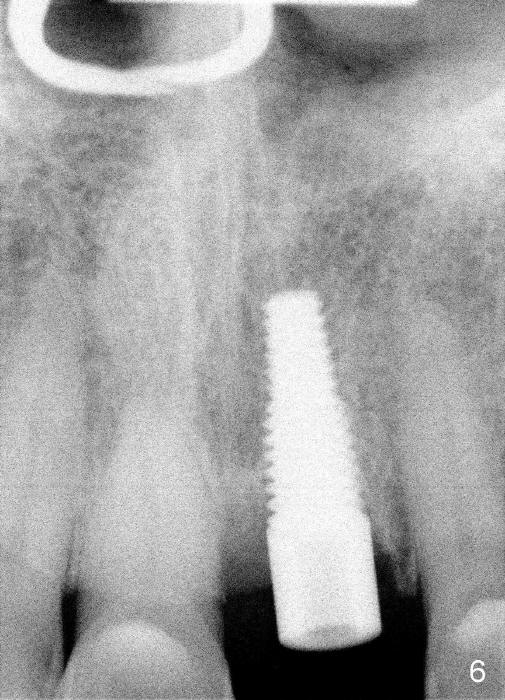

After extraction, osteotomy is made as palatally as possible so that the end of a reamer/drill (Fig.3 R) in the line of the incisal edge of the neighboring teeth. The depth of the 3.5 mm reamer is 14 mm from the crest (Fig.4 <). Next, a 5x17 mm tapered implant is placed with insertion torque > 60 Ncm (Fig.6). A 4 mm 0° unipost is permanently cemented (Fig.5: P). Finally a provisional is cemented on a temporary basis (Fig.7,8: T). There is no contact in centric or any lateral excursions.